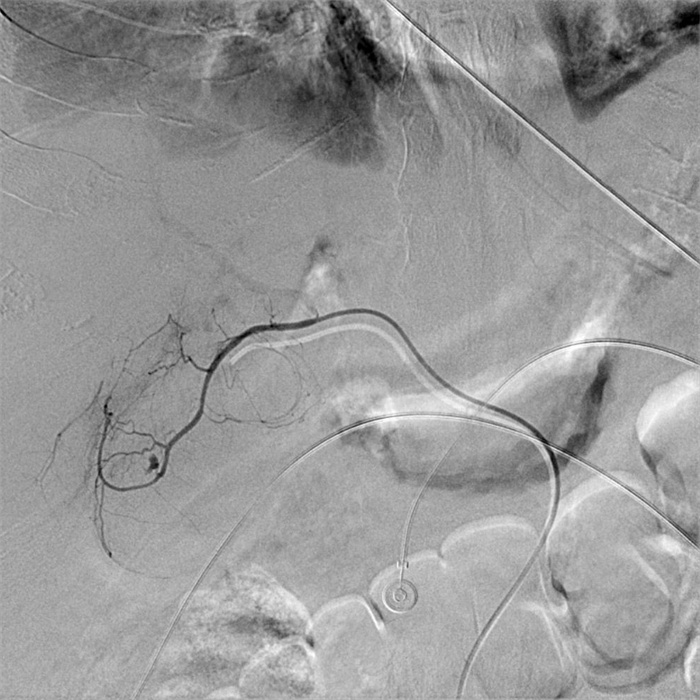

入院第57天,患者再次出现暗红色血便,伴阵发性右上腹痛,无发热、呕血,症状与之前相同。鉴于患者有活动性出血,再次复查胃镜:慢性浅表性胃炎伴糜烂。复查肝功能:γ-GT 844 U/L,TBil 43.6 μmol/L,NCBil 16.6 μmol/L,CBil 27 μmol/L,肝功指标再次回升,γ-GT、CBil明显升高,提示可能出现胆道梗阻。肝胆脾胰腺彩超复查:胆囊肿大、胆囊陈旧性稠厚淤胆(较前无明显变化),胰腺稍大并不均质改变。复查上腹CT:AP复查情况与之前相同,可能有胆囊出血(见图 2)。联合介入放射科行血管造影检查,常规局部麻醉下采用Seldinger技术由右侧股动脉入路,造影发现胆囊动脉分支出血(图 3),超选择胆囊动脉分支用明胶海绵颗粒行栓塞止血(图 4)。同时,行经皮经肝胆囊穿刺置管引流(图 5),病情稳定后带管出院,3月后予以拔除,择期行胆囊切除。

| 栓后造影胆囊动脉主干以远闭塞,造影剂外溢征象消失 图 4 胆囊动脉介入栓塞术后复查造影 |

胆囊动脉出血是罕见的胰腺炎血管并发症,确切的病理基础尚不清楚,推测其出血的机制主要继发于胰管释放的胰酶侵蚀及炎症刺激损伤血管壁[4]。介入放射科的共同参与在复杂胰腺炎的救治中有着重要作用[8],胆囊动脉出血难以被常规的检查发现,尤其是经常规治疗后患者仍有活动性出血时,选择性血管造影应作为首选方法。血管造影仍然是目前判断有无活动性出血的“金标准”,敏感度可达80%~90%以上[9]。血管造影同时发现异常血管、急性出血病因及部位[10],发现病灶的同时可给予介入治疗,有助于迅速维持血流动力学稳定。

Thillai等[11]报道胆囊动脉出血给予栓塞治疗后会出现胆囊坏疽、继发腹腔感染的情况,本例患者行胆囊动脉栓塞后同时给予胆囊穿刺置管引流及冲洗治疗,未出现其报道的继发感染情况,后择期行胆囊切除术。